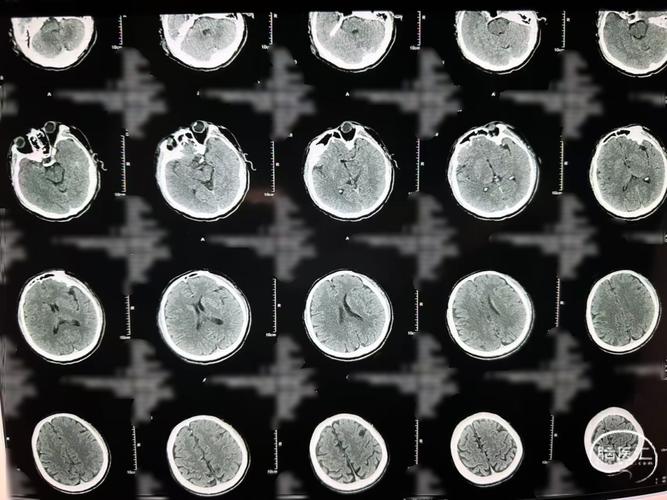

看CT片子的基本准备

在看片子之前,我们先要了解几个基本概念:

- CT是什么? CT(计算机断层扫描)是利用X射线对大脑进行分层扫描,通过计算机处理后形成图像,它像给大脑切了一片片“面包”,我们能从不同角度看到里面的结构。

- 正常脑CT是什么样的?

- 灰质与白质: 大脑表面颜色较深的区域是灰质(神经元细胞体聚集地),内部颜色较浅的区域是白质(神经纤维束聚集地),它们之间界限清晰。

- 脑沟与脑裂: 大脑表面的沟壑,正常情况下清晰可见。

- 脑室与脑池: 中间是空的脑室系统(如侧脑室、第三脑室),里面充满脑脊液,在CT上显示为黑色低密度区。

- 密度: CT图像上用不同的灰度来表示不同的密度。

- 高密度(白色): 骨头、钙化、新鲜出血。

- 等密度(灰色): 脑组织、急性血栓。

- 低密度(黑色): 脑脊液、脑水肿、脑梗塞后的软化灶。

如何区分“腔梗”和“脑梗”的CT表现

腔隙性脑梗塞

腔梗是一种非常小的梗塞,通常是由于大脑深部的小穿支动脉阻塞引起的,梗塞灶直径一般在 5-2厘米以下。

CT表现特点:

- 病灶位置:

- 非常关键!几乎都发生在大脑深部,比如基底节区、丘脑、脑干、放射冠等,这些区域正是小穿支动脉的供血区。

- 病灶大小:

- 非常小,在CT上通常表现为一个或数个点状、圆形或卵圆形的低密度影,如果病灶特别小(小于3-5毫米),在常规的CT上可能完全看不到,这就是为什么很多腔梗患者在做头颅CT时报告“未见明显异常”。

- 病灶形态:

形态规则,边界相对清晰,呈“小洞”或“小点”状。

- 占位效应:

- 没有或极其轻微,因为病灶太小,不会对周围脑组织产生明显的挤压,所以不会导致脑中线移位或脑室受压变形,这是它与较大脑梗的一个重要区别。

- 时间窗:

- 发病24小时内,CT可能阴性(看不到),只有在梗塞发生几天后,脑组织开始坏死液化,形成软化灶时,CT才能清晰地显示为低密度影。

一句话总结腔梗CT: 大脑深部的小点状、无占位效应的低密度影。